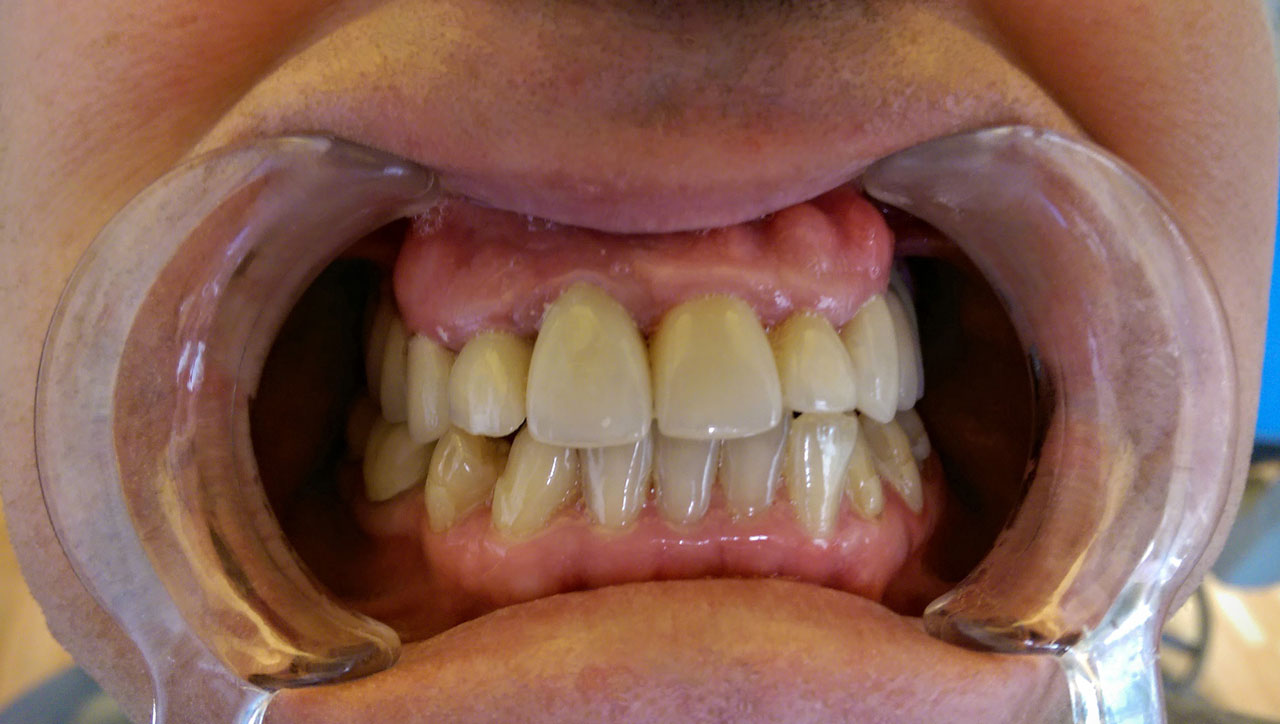

Teljes fogatlanság helyreállítása 2 nap alatt

Teljes fogatlanság helyreállítása 2 nap alatt azonnal terhelhető svájci IHDE implantátumokkal és PMMA műanyag hidakkal. Intraorális szkennerrel vettünk lenyomatot az implantáció után, és erre a digitális mintára készítette el a fogtechnika a hidak digitális tervezését, majd faragta ki műanyagból. Ezt a gyors munkát az azonnal terhelhető implantátumok és a digitális lenyomat, tervezés segítségével tudtuk megcsinálni mindössze 2 nap alatt. Dr. Kelemen Péter és a Symbion Fogtechnika munkája.